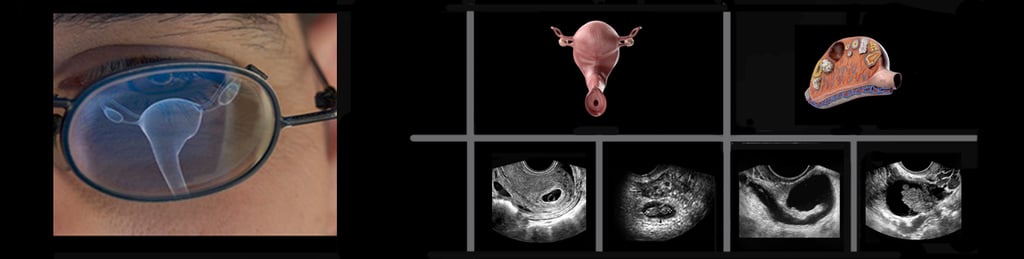

Hands-On Transvaginal Pelvic Ultrasound Imaging & Doppler

A single-day guided experience that develops the skill to evaluate pelvic anatomy and physiology accurately, confidently, and with disciplined clinical reasoning.

This is where precision, confidence, and women's care converge. We’ve developed one of the most effective live, hands-on transvaginal ultrasound training experiences available today. In this course, you’ll learn how to perform a complete, efficient, and accurate pelvic exam—from the first image to the final Doppler sweep.

Step-by-step pelvic imaging of the uterus, adnexa, Pouch of Douglas, bladder, and pelvic floor.

Safety, optimization and practical use of color, spectral, and power Doppler.

Consistent, accurate ovarian identification—every time.